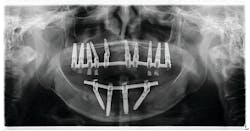

- All-on-4 (AO4) or a full-arch hybrid prosthesis that is fixed (figures 4 and 5).

- Single implants across the arch in various positions to which single-tooth and bridge entities are fixed to mimic the natural dentition in a more natural way.